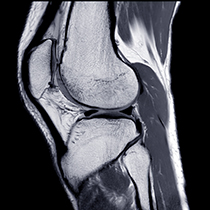

RMN extremitati

Investigatia poate evidentia afectiuni ale sistemului osos sau articular, posibile afectari ale cartilajului, rupturi de tendoane sau ligamente, tumori osoase.